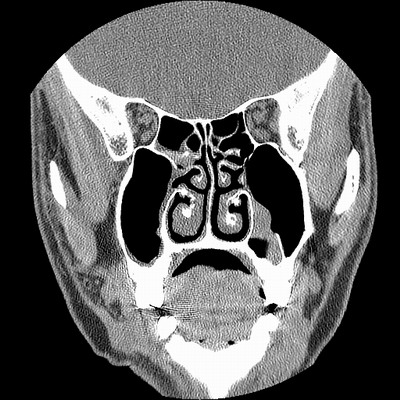

男,38岁,鼻塞、头痛2个月,要求鼻窦ct检查。

右侧上颌窦、蝶窦、筛窦、额窦及左侧上颌窦慢性炎症。

右侧鼻中隔左偏,右侧上颌窦、筛窦、额窦慢性炎性病变。右侧上颌窦开口粘膜增厚。

1)副鼻窦炎。2)右侧中鼻道及总鼻道粘膜息肉样变。3)双侧中下鼻甲肥大。4)鼻中隔轻度左突偏曲。